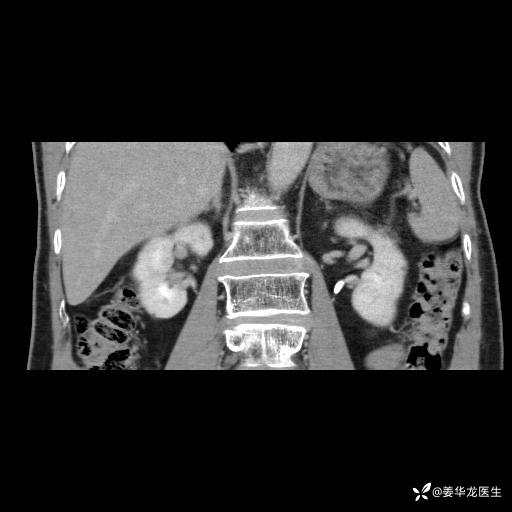

左肾中心型肾门部肿瘤39mm×34mm×36mm,右肾GFR25ml/min,部分切还是全切?

患者75岁老年男性,体重50kg,无高血压、肾病、糖尿病等基础病,检查发现左肾中心型肾门部肿瘤,右肾GFR只有25ml,无肉眼血尿,无镜下血尿。入院验血常规检查均正常,包括肾功能,肌酐102.7umol/L.

二、左肾肿瘤与左肾集合系、左肾动静脉关系密切,左肾部分切除术可行吗?成功率有多大?成功部分切后,肾功能还有多少?